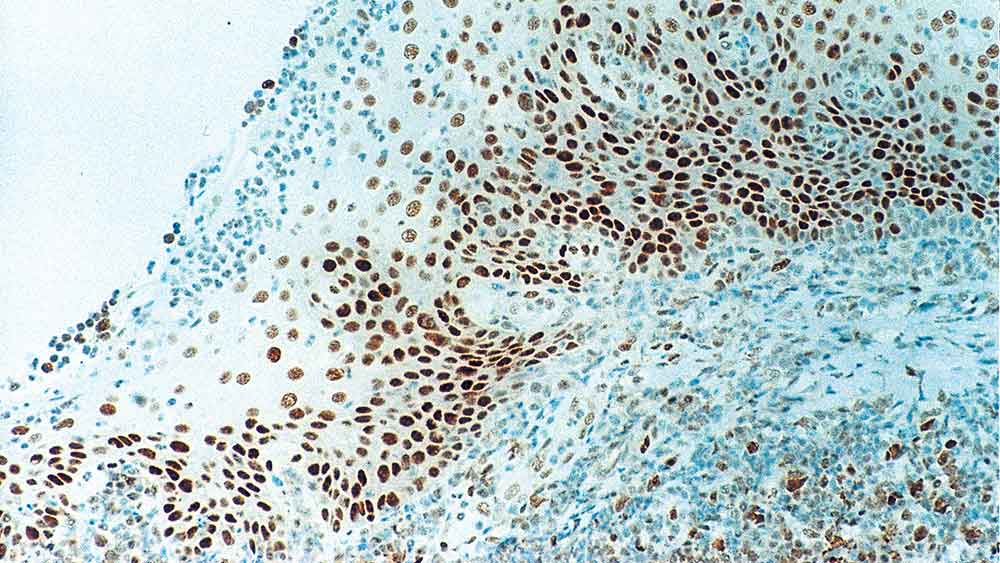

Human tonsil: immunohistochemical staining for Retinoblastoma Gene Protein. Note intense nuclear staining of epithelial cells. Retinoblastoma Gene Protein: clone 13A10

Retinoblastoma (Rb) is a rare tumor of the retina associated with mutations of chromosome 13. The nuclear phosphoprotein encoded by the Rb tumor suppressor gene is present in many cells and may indirectly regulate cell growth by activating the transcription factor ATF-2. Activation of ATF-2 initiates expression of TGF-beta2, which in turn inhibits transcription of genes affecting cell growth. Bilateral mutation of the Rb gene may potentially play a role in the development of a number of malignant tumors.